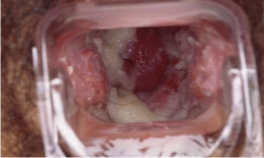

Angiomatosis bacilar: Bartonella Helensae

Angiomatosis bacilar